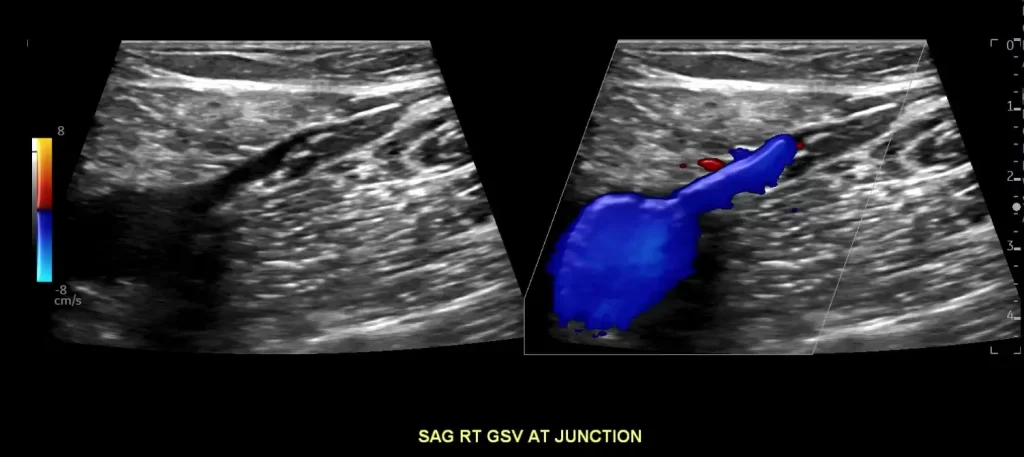

If you suspect a clot in a superficial vein, the next step is to get an ultrasound. There are two reasons for this. First, because the ultrasound will prove the diagnosis. But second, ultrasound will also show the clot extent. It is important to understand if the clot is extensive or if it is localized. It is also important to know if the clot is close to the deep veins, or if it is only in the superficial veins.